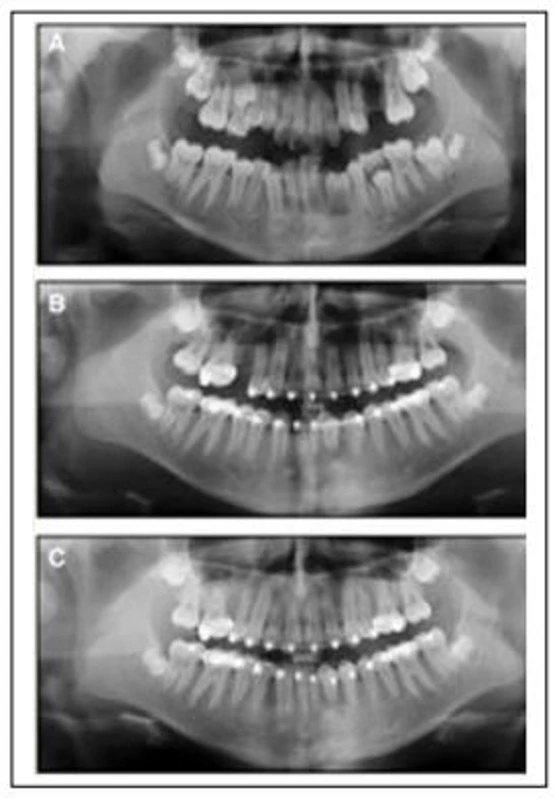

Khi dây cung Niti trở nên thụ động trong tất cả các khe mắc cài ở cả hai dây cung, thì bạn sẽ phải xác định lại xem mắc cài đó được gắn đúng chỗ hay không. Nếu mắc cài đã được gắn đúng, thì không còn răng nào bị xoay nữa. Nếu mắc cài nào bị gắn sai chỗ thì cần phải gắn lại để chỉnh lại xoay sai hoặc góc sai. Góc mắc cài bị sai được định giá bằng phim Panorama tiến trình, hoặc mẫu nghiên cứu tiến trình. Sai sót về chiều cao một răng nào đó có thể không cần phải gắn lại, vì những sai sót này sẽ được sửa dễ dàng trong giai đoạn hoàn tất.

Máy X quang cận chóp Veraview IX

Sai sót về chiều cao mắc cài của cả phân đoạn răng có thể sẽ yêu cầu gắn mắc cài lại để tránh sai sót tiếp theo trong tiến trình điều trị. Sai lầm phổ biến nhất là khi người học đặt vị trí mắc cài từ răng 3 đến răng 3 cung dưới quá gần lợi để tránh cắn chạm lên răng cửa trên. Nếu để lại sai sót này sẽ chống sửa cắn sâu, và có thể gây ra các vấn đề cản trở làm nhô vùng răng cửa trước.

Học viên phải lấy mẫu nghiên cứu triến trình vào cuối giai đoạn làm thẳng để kiểm tra về vị trí đặt mắc cài để người hướng dẫn kiểm tra. Dấu lấy bằng alginate bất kì tại phòng mạch và đổ mẫu mài chỉnh tại xưởng. Cần lấy dấu sáp cắn để mài mẫu theo tương quan, để tái lập cắn trung tâm bằng việc đặt mẫu lên bàn phẳng. Đối với những học viên điều trị những ca đầu tiên thì có thể cần phải gắn lại một số mắc cài.